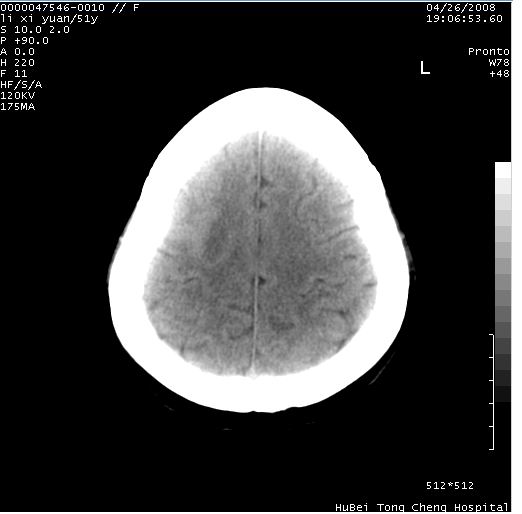

以下是引用余辉在2008-4-27 14:02:00的发言:[br]病灶位于中央沟前方?位于额叶?高密度灶,灶周水肿不明显,病灶似沿脑沟走行,强化明显,局部层面呈现环状强化,考虑1脑表面血管性疾病,如血管瘤,血管扩张,灶内血栓形成,其次考虑肿瘤如脑膜瘤、转移瘤,胶母等

以下是引用形影不离在2008-4-27 14:13:00的发言:[br]考虑胶质瘤可能性大,不排除慢性炎性肉芽肿。建议mri检查。